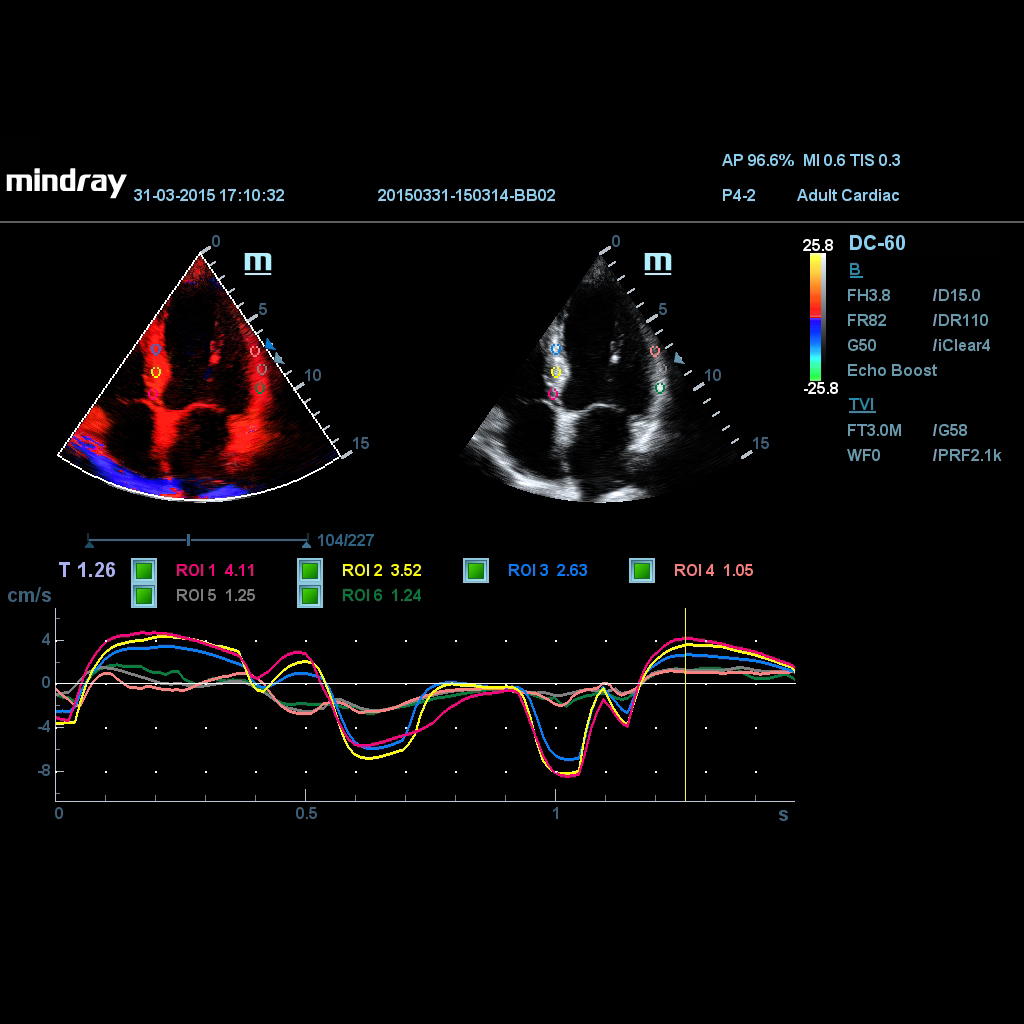

TDI QA се прилага за анализ на оригиналните данни на TVI, за оценка на промяната на скоростта на същия сърдечен мускул със сърдечните цикли.